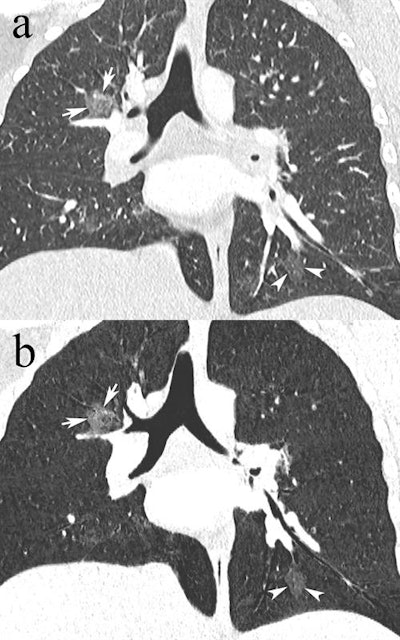

In consensus, two blinded radiologists reviewed the CTPAs of 229 patients with regard to PE, alternative diagnoses, and technical quality. The researchers found that 16 patients (7%) had PE, 144 (62.9%) had no abnormal findings, and 69 (30.1%) had an alternative diagnosis such as consolidation, other pulmonary opacities, pleural effusion, and basal atelectasis.

Among the 213 patients without PE, 35 (16.4%) had a single alternative diagnosis, while 34 (16.0%) had multiple alternative diagnoses.